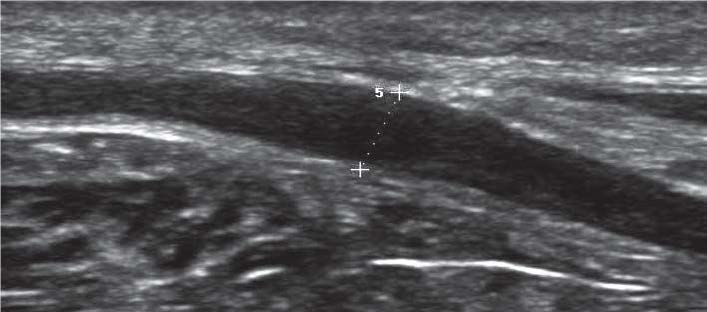

У 7 пациентов дооперационно была диагностирована причина нарушения функции лучевого нерва – сдавление нервного ствола под пластиной после лечения диафизарного перелома плечевой кости (рис. 2). Однако во время операций было установлено, что у двух пациентов нервный ствол не находился под пластиной, а проходил сбоку от неё, плотно прилегая к краю пластины. Ошибочное заключение УЗИ связано с частичным экранированием нервного ствола акустической тенью от металлической пластины.

Рис. 2. Поперечные эхограммы лучевого нерва (фигурная скобка) на уровне средней трети плеча с наличием пластины (стрелка) над нервным стволом